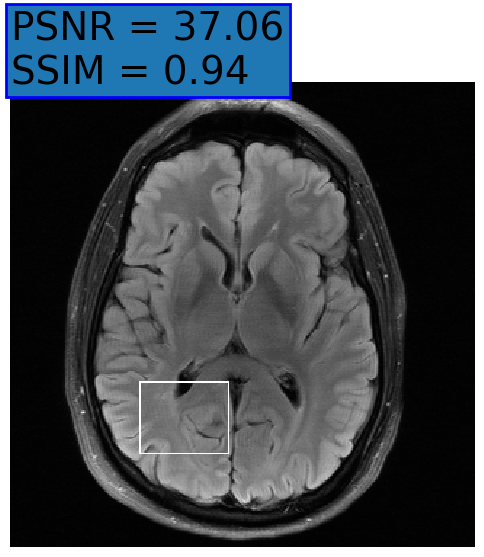

Figure 3: Reconstructions results. Rows 1 and 3: Examples of comparing the ground truth (GT) fully sampled image to the reconstructed images obtained by the three models (1-3), NPB-REC, baseline, E2E-VarNet trained with Dropout, and the NPB-REC std. map at accelerations R=4𝑅4R=4italic_R = 4, R=8𝑅8R=8italic_R = 8, respectively. Rows 2 and 4: The corresponding annotated ROIS of Nonspecific white matter lesions.

Fig. 3 presents examples of reconstruction results obtained by (1) our NPB-REC approach, (2) the baseline, and (3) Monte Carlo Dropout, for equispaced masks with two different acceleration rates R=4𝑅4R=4italic_R = 4 and R=8𝑅8R=8italic_R = 8. The reconstructed images predicted by the three models are smoother than the reference image. This is due to the fact that all the models were trained with SSIM loss, which tends to produce overly smooth reconstructions while preserving the diagnostic content and the anatomical features Sriram et al. (2020a). These images can be enhanced by dithering the image by adding a small amount of random Gaussian noise to produce a more textured reconstruction, as proposed in Sriram et al. (2020b).

Table 1 presents the mean PSNR and SSIM metrics, calculated over the whole inference set, for the three models. Our NPB-REC approach achieved significant improvements over the other methods in terms of PSNR and SSIM (Wilcoxon signed-rank test, pmuch-less-than\ll1e-4, except for SSIM values in line W, R=4𝑅4R=4italic_R = 4 where they are roughly the same for NPB-REC and Baseline). The improvement in the reconstruction performance can be noted both quantitatively from the metrics, especially for masks with acceleration rate R=8𝑅8R=8italic_R = 8, and qualitatively via the images of annotations, where our results show less smoothness than those obtained by Dropout.